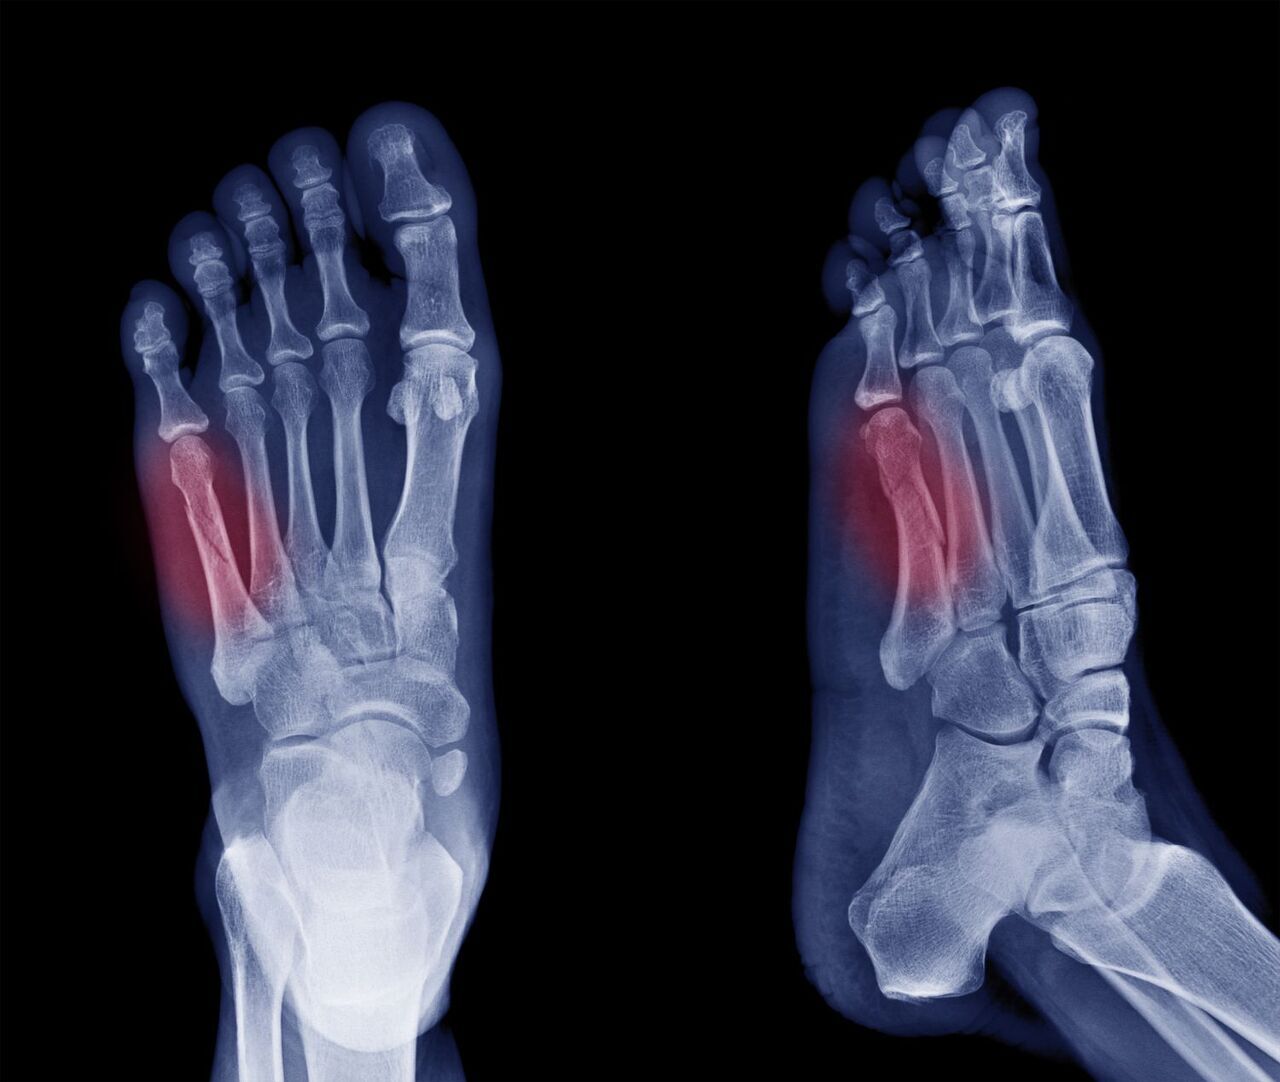

발가락 골절의 원인 및 증상

발가락 골절 역시 여러 원인으로 인해 발생할 수 있으며, 그중 가장 흔한 원인은 무거운 물체가 발가락에 떨어지는 경우입니다. 운동 중 부상, 실족하여 발가락이 끼이는 사고, 혹은 신발이 맞지 않아 발생하는 골절도 있습니다.

발가락 골절의 증상으로는 발가락 부위의 심한 통증, 부기, 멍, 발가락의 변형, 걷기 어려움 등이 있습니다. 또한, 골절된 부위를 움직일 때 통증이 더욱 심해질 수 있습니다.

손가락과 발가락 골절의 치료 방법은 골절의 유형과 심각도에 따라 다를 수 있습니다. 가벼운 골절의 경우, 통증을 줄이고 골절이 올바르게 치유될 수 있도록 고정하는 것만으로 충분할 수 있습니다. 이를 위해 붕대를 감거나 보호대를 사용하여 골절된 부위를 고정시킬 수 있습니다. 중증도의 골절이나 복잡한 골절의 경우, 수술적 치료가 필요할 수 있으며, 핀이나 금속판을 사용하여 골절 부위를 고정시키는 방법이 사용될 수 있습니다.

손가락 발가락 완치 기간은 골절의 심각도, 치료 방법, 개인의 건강 상태 등에 따라 달라질 수 있으나, 일반적으로 손가락이나 발가락 골절의 경우 대부분 4주에서 6주 사이에 뼈가 붙기 시작합니다. 하지만 완전히 정상적인 기능을 회복하기까지는 더 긴 시간이 필요할 수 있으며, 때로는 3개월 이상 걸릴 수도 있습니다. 또한, 복잡한 골절이나 수술이 필요한 경우 회복 기간은 더욱 길어질 수 있습니다. 정확한 손, 발가락 치료 기간은 환자의 나이, 건강 상태, 골절의 위치와 종류, 치료 방법 등에 따라 달라집니다.